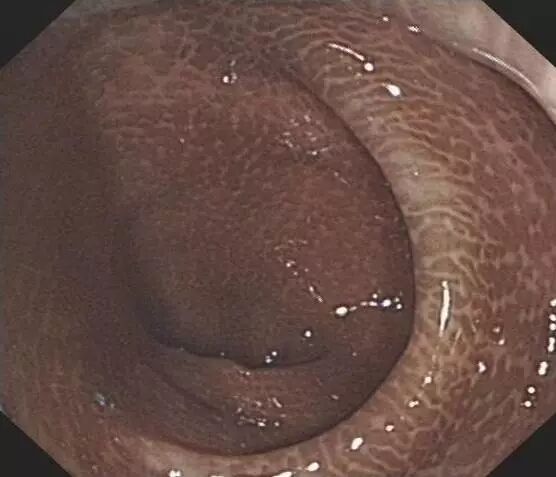

▲正常人的结肠VS 黑变病结肠▲

辣不辣眼睛?